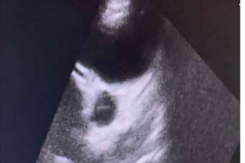

Initial complete blood count showed moderate normochromic and macrocytic anemia (hemoglobin: 8.9 mg/dL, MCV: 91.6 fL, MCHC: 32.6 g/dL), leukocytosis (white blood cells: 18,800/mm3), lymphopenia (lymphocyte count: 11.5% with an absolute lymphocyte count [ALC] of 2,162 cells/mm3), elevated inflammatory markers (CRP: 96 mg/L, ESR: 80 mm/h), elevated creatinine (0.93 mg/dL), abnormal coagulation parameters (D-dimer: 1,947 ng/mL, INR: 4.07, PT: 38.3 s), and abnormal liver function tests (total bilirubin: 0.42 mg/dL, AST/GOT: 50 U/L, ALT/GPT: 107 U/L). The post-COVID-19 Multisystem Inflammatory Syndrome diagnosis was made, even though COVID-19 PCR and serology results for IgM were negative, as IgG was positive. Other tests, including troponin I, COVID-19 antigen, and rapid malaria test, were also negative. Urine and blood cultures were sterile. She underwent two echocardiograms: the first one before her transfer showed mild to moderate mitral regurgitation, right coronary artery dilation at 6 mm, left coronary artery dilation at 5 mm, and a z-score of 5 (Images 3 and 4). The second echocardiogram, performed one week later, indicated probable post-infectious myopericarditis. Chest radiography revealed infiltrates.

Image 4: right coronary artery dilation at 6 mm, left coronary artery dilation at 5 mm, and a z-score of 5